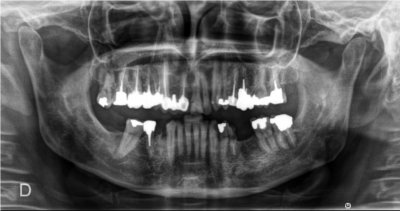

Images de panoramiques dentaire:

-pour le panoramique dentaire l'appareil tourne autour de vous, votre tête est installée dans l’appareil et maintenue par un système de contention. Une pièce en plastique sera placée entre vos dents de manière à ce que vous mâchoires soient légèrement écartées. L’acquisition du cliché dure environ 10 à 20 secondes durant lesquelles vous devez rester immobile.

- implants dentaires

Le cone beam utilisé en pathologie dentaire et maxillo-faciale est indiqué pour l’examen des tissus minéralisés (dents, cartilages, os), il permet d’identifier les lésions osseuses, les fractures, les infections, les kystes ou les corps étrangers.

Il est un examen de choix en implantologie.

Il évalue au plus juste le volume osseux et la position des structures anatomiques comme les nerfs en vue de la pose d’implants. La modélisation en 3D permet la taille et la forme des implants proportionnellement à la morphologie du patient et de simuler virtuellement leurs emplacements.